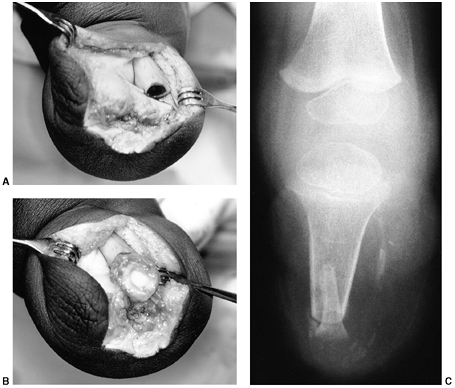

to provide a healthy soft-tissue envelope. (Fig. 31.2).

Figure 31.2 A, B:

The end of the tibia with the bony overgrowth removed and the head of the fibula inserted into the medullary canal of the tibia (Marquardt procedure). C: The anteroposterior view of the tibia 6 weeks after the procedure. |